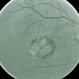

- laser treatment, recurrence

- No history, this is before treatment.